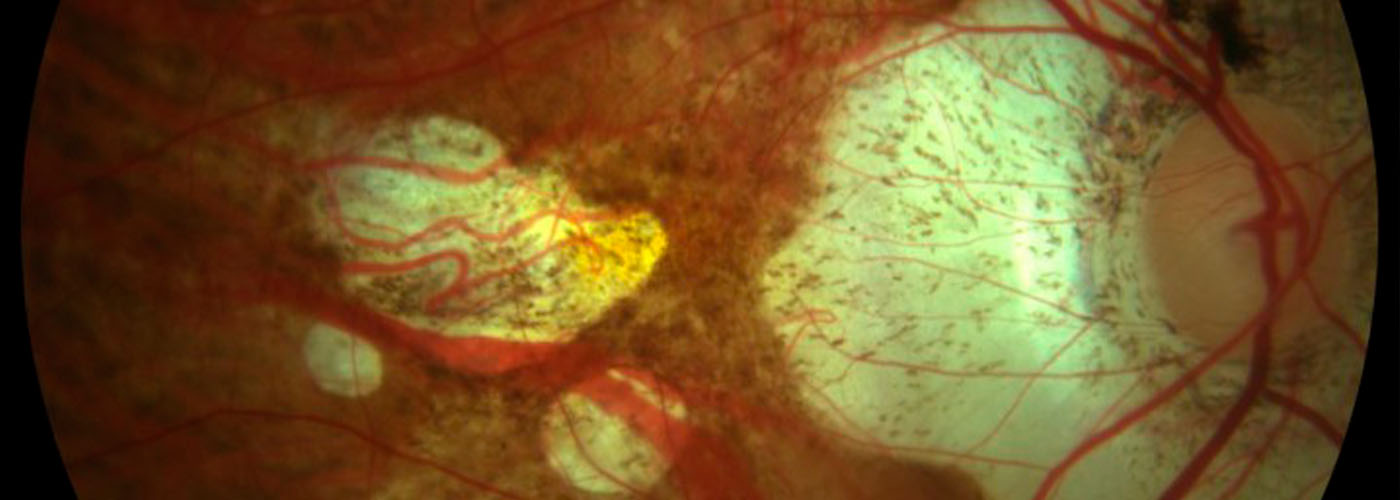

Al trabajar en un centro de optometría, intento hacerme controles habitualmente. Relacionado con la diabetes, una vez al año me hago una retinografía y luego consulto al especialista si es necesario.